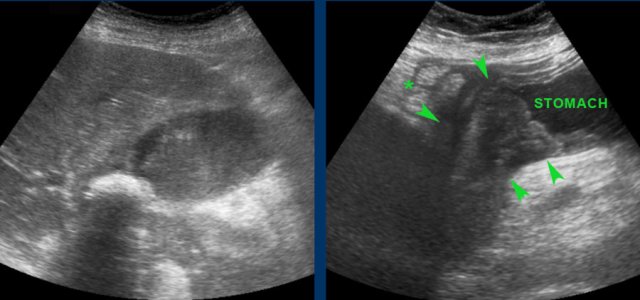

Here images of a patient with acute hydrops of the gallbladder, visualized in its longitudinal and its axial plane.

The obstructing stone is impacted (arrow).

Note that during compression the hydropic gallbladder bulges into the abdominal wall (arrowheads), indicating high intraluminal pressure.

It is however not always possible to visualize the hydrops-sign reliably, especially when the gallbladder lies high under the right costal arch.

Also the impacted stone may be impossible to visualize in large persons, due to its deep location, far from the transducer.

Not infrequently, also on CT scan hydrops of the gallbladder may be identified (fig), but often complementary US is very useful.

Here images of a patient with clinically suspected stomach perforation.

CT shows some stones in a rounded gallbladder.

Complementary US unequivocally demonstrates hydrops (arrowheads).